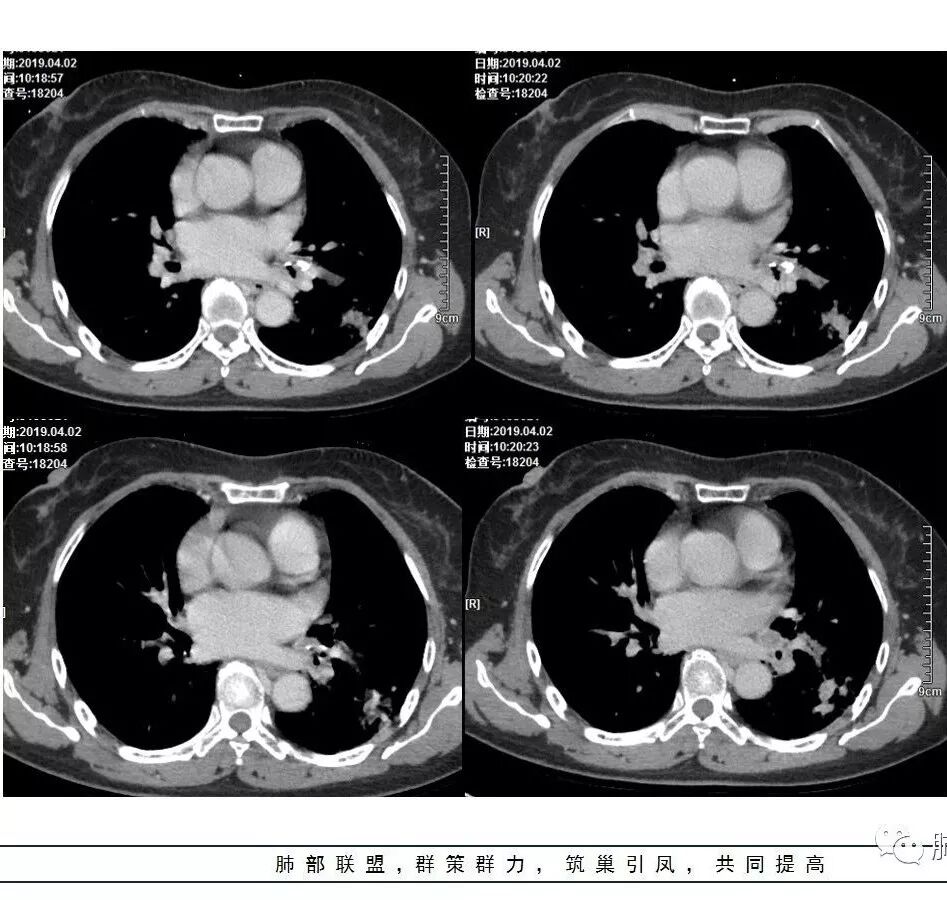

2.左肺下叶片状影及多数有边界的结节影,较散,多形性,密度不均(注意许多老师提到这个特点还是比较明显的)。左肺下叶体积未见缩小。

3.病灶强化比较明显。

4.左下叶支气管壁增厚,管腔不均匀狭窄,没有堵塞

5.肺门纵隔见增大钙化淋巴结。提示曾经存在慢性病损可能。

1.前述特点除强化外都还是很容易让人首先想到肺结核的可能性。结核是常见病。注意肉芽肿明显的结核灶可以观察到强化。

2.淀粉样变性病变支气管改变一般会更广泛,较少出现单叶肺的如此大片影。

3.腺癌不大会出现较散的腺泡样结节影,更不会出现如本例的支气管改变。增大钙化的淋巴结也很难相互关联。

4.相关支气管未见腔内结节及阻塞,女性患者,鳞癌的可能性更小。